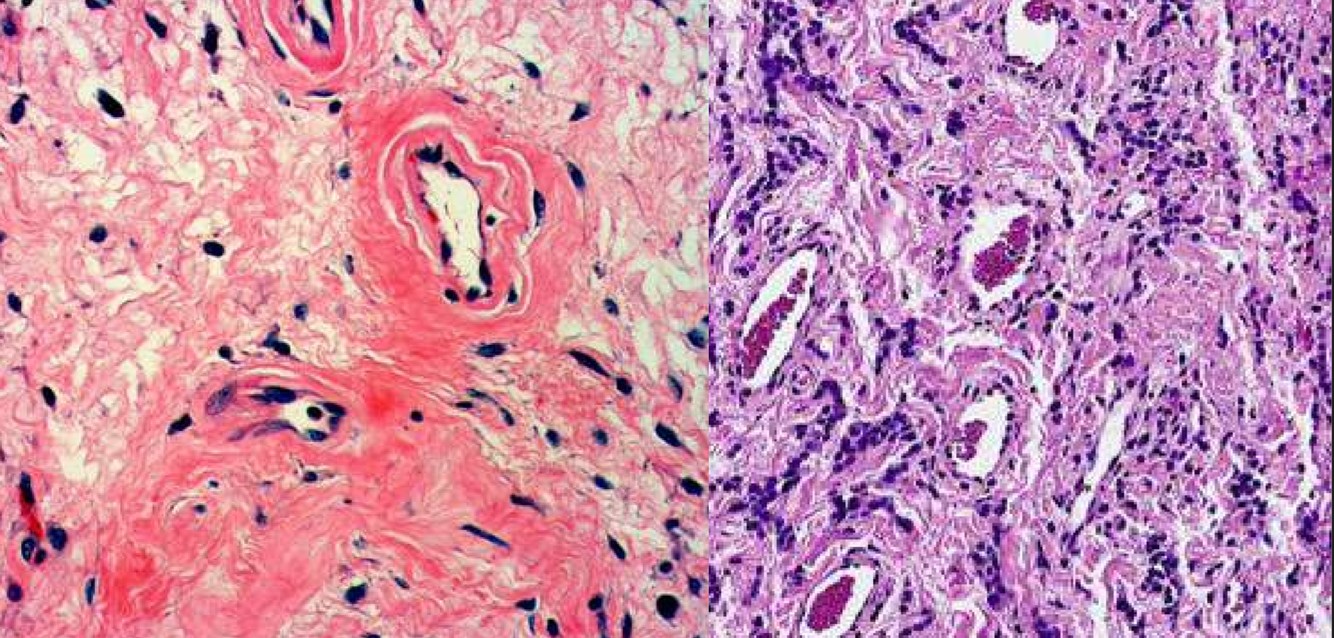

AGGRESSIVE ANGIOMYXOMA

Angiomyofibroblastoma

Angiomyofibromyxoma vs. Aggressive Angiomyxoma

Angiomyofibromyxoma

• circumscribed border

• higher cellularity

• frequent presence of plump stromal cells

• lesser degree of stromal myxoid change

• lack of RBC extravasation